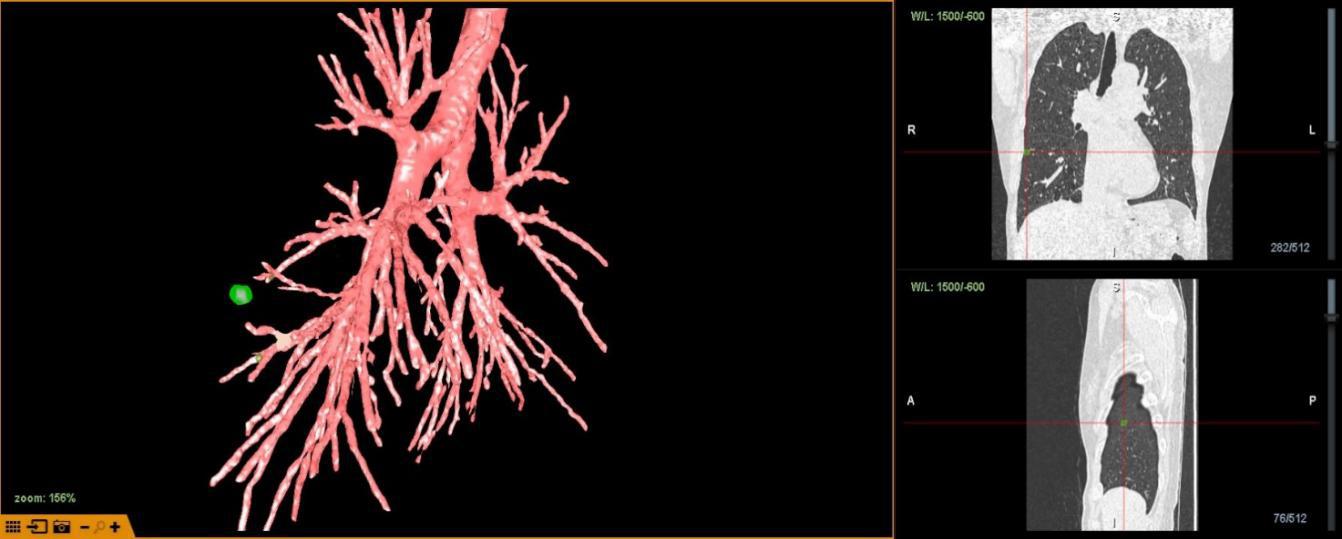

为精准术前规划,在LungPro导航系统重建患者支气管、肺结节的基础上,潘小杰主任带领胸外科团队就病灶的位置、如何制定最优路线进行深入分析及讨论,充分评估病灶及染色的位置、距离等。

LungPro增强现实支气管镜导航系统,可以借助血管重建投影技术以及独有的隧道技术穿出气管,到达全肺,而且不用借助磁场,费用低。